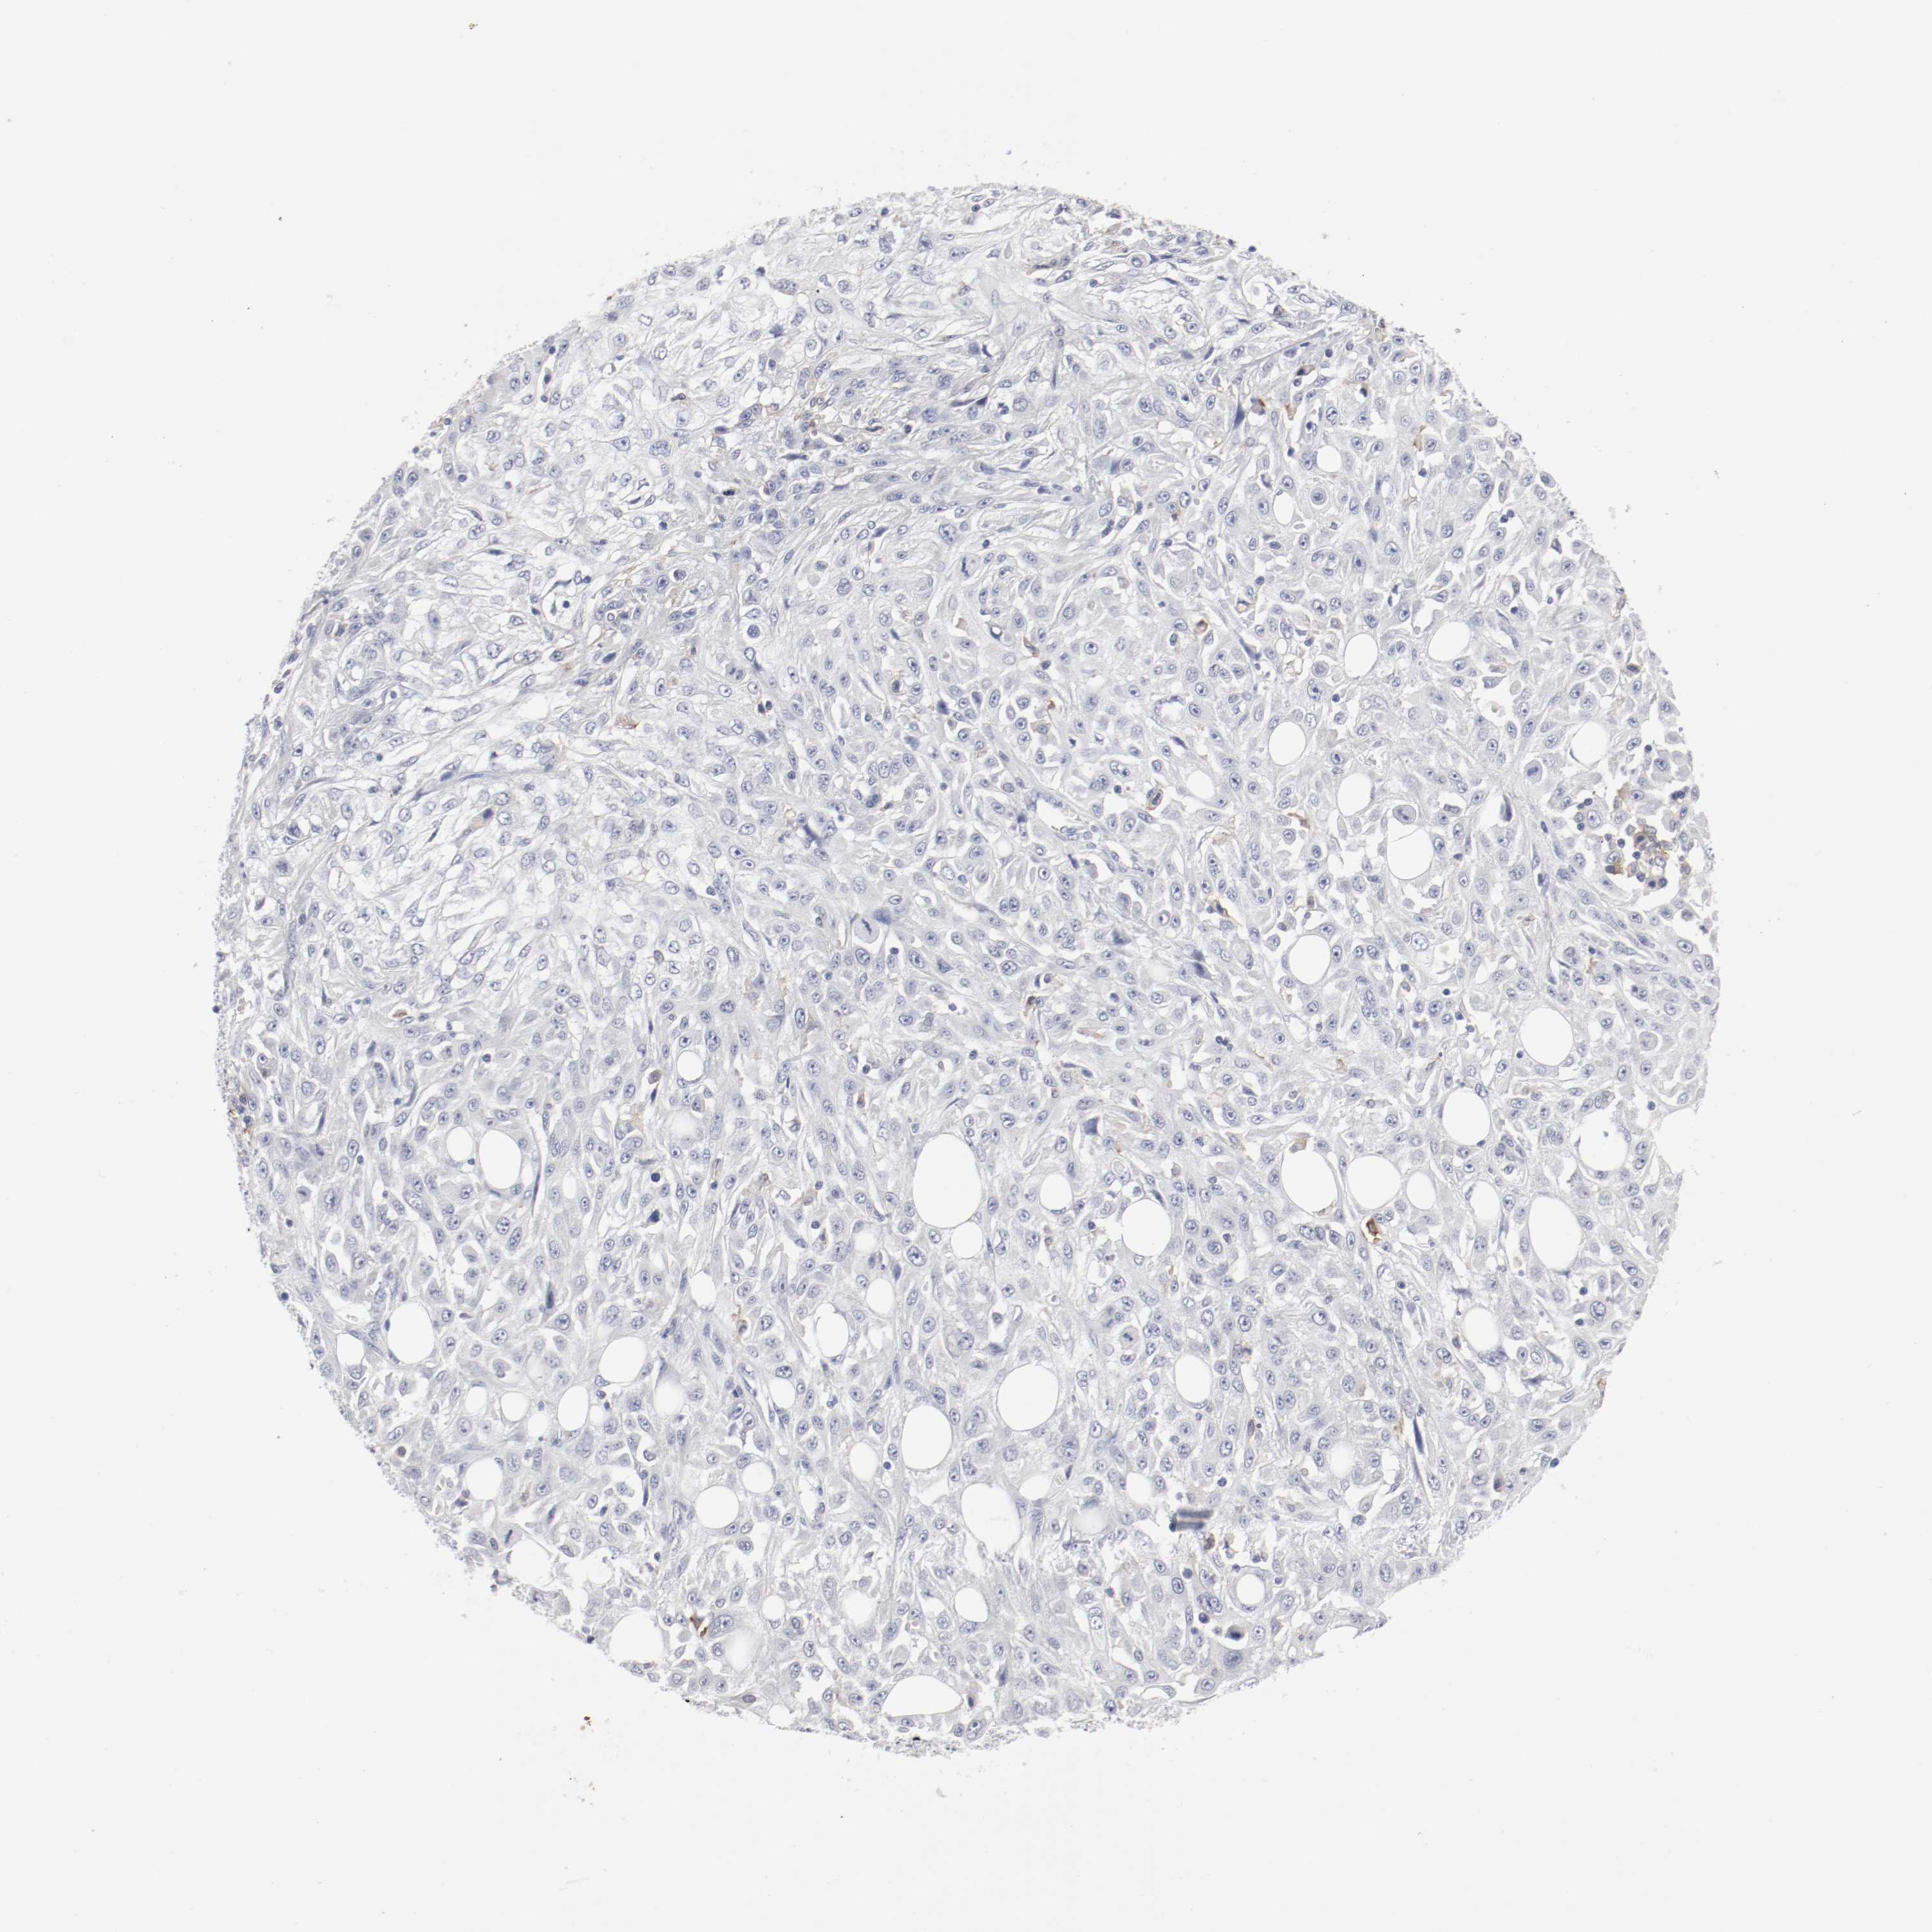

SKIN CANCER - Protein expressioni

A mouse-over function shows sample information and annotation data. Click on an image to view it in a full screen mode. Samples can be filtered based on level of antibody staining by selecting one or several of the following categories: high, medium, low and not detected. The assay and annotation is described here.

Antibody stainingi

Antibody staining in the annotated cell types in the current human tissue is reported as not detected, low, medium, or high, based on conventional immunohistochemistry profiling in selected tissues. This score is based on the combination of the staining intensity and fraction of stained cells.

Each image is clickable and will lead to virtual microscopy that enables deeper exploration of all samples and also displays staining intensity scores, fraction scores and subcellular localization as well as patient and tissue information for each sample.

Antibody HPA004723

Squamous cell carcinoma, NOS

Basal cell carcinoma